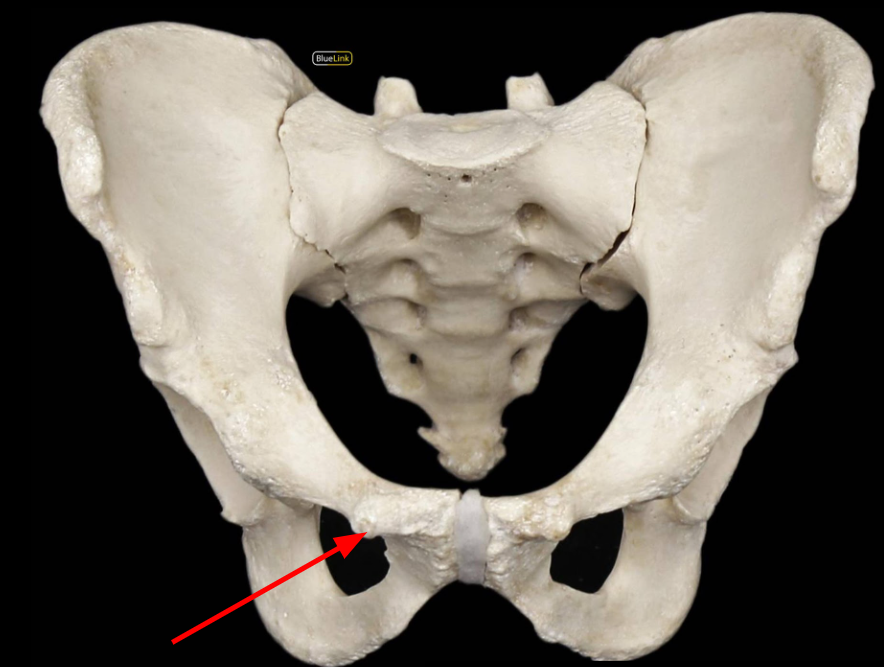

Pubic Symphysis

Ischiopubic Ramus